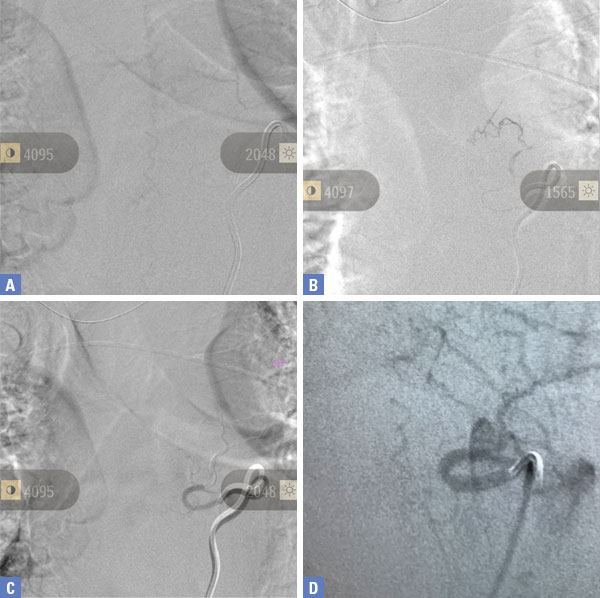

Based on the MRI findings and the clinical presentation, a spinal dural fistula was presumptively diagnosed and a spinal angiogram recommended with planned attempt to embolize a fistula if encountered. Spinal angiography confirmed a spinal dural fistula fed from radiculomedullary branches off the left T6 pedicle and draining into a spinal vein (Figure 2B & 2D).

No spinal arteries were identified from this pedicle and after provocative testing with lidocaine and amytol injection confirmed that no arterial input to the spinal cord, the fistula was sealed with one injection of onyx glue (Figure 2C). Post-embolization angiogram confirmed no residual filling of the fistula (Figure 2D).

Pre-Treatment (Figure 2A and 2D), At Treatment (Figure 2B – Onyx Glue Cast), and PostTreatment (Figure 2C)